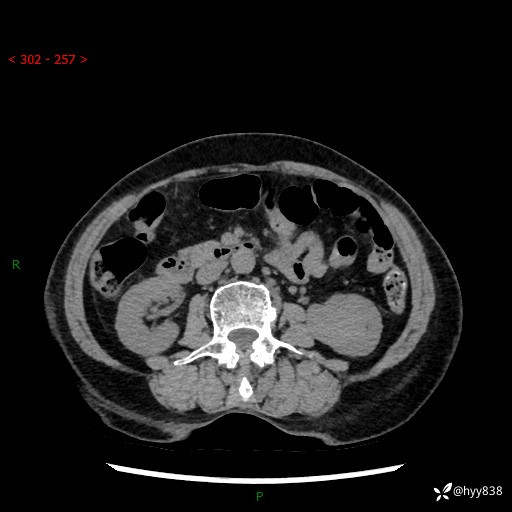

72岁/女,检查发现左肾占位1天。为了满足诊断,常规四期后,又加了延迟期-结果公布~

【患者信息】:72岁/女

【主诉】:检查发现左肾占位1天

【现病史及既往史】:患者于1天前检查发现左肾占位,无畏寒发热,无咳嗽咳痰,无腰腹部疼痛不适,无肉眼血尿、无尿频尿急症状,起病来,患者未行特殊治疗,为求进一步诊治,门诊以"左肾占位"收治入院。 发病来患者精神、饮食、睡眠良好,小便如上,大便正常,体重无明显变化。

【检查】:肾脏CT平扫+增强